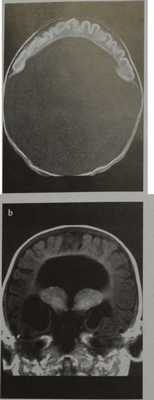

Алобарная голопрозэнцефалия:

- Слияние таламусов

- Отсутствуют третий желудочек, продольная щель, серп большого мозга и мозолистое тело

- Большой мозг припаян к ростральному отделу полости черепа

- Один большой желудочек, сообщающийся с большой задней кистой

- Возможно также слияние орбит

- Непарная передняя мозговая артерия.

а) При алобарной голопрозэнцефалии в результате неразделения таламусов отсутствует III желудочек. Не определяют межполушарную борозду, серп и мозолистое тело. Расположение вещества мозга вокруг единственного желудочка создает картину, напоминающую подкову. В задних отделах расположена киста. Причиной формирования дорсальной кисты служит окклюзия на уровне промежуточного мозга. При МР-ангиографии - единый ствол передних мозговых артерий.

а) Алобарная голопрозэнцефалия - отсутствие серпа мозга, межполушарной борозды и мозолистого тела. Единственный расширенный желудочек переходит в большую дорсальную кисту, которая может быть причиной макроцефалии. Вещество мозга присутствует только в лобных отделах по периферии единственного желудочка. Таламусы не разделены, III желудочек отсутствует.